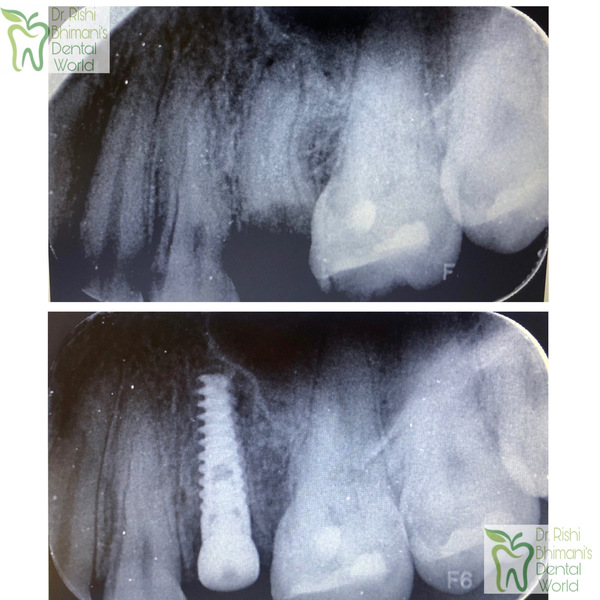

IMMEDIATE DENTAL IMPLANT DENTAL IMPLANTS can repla...

DENTAL IMPLANTS DENTAL IMPLANTS can replace a sing...

DENTAL IMPLANTS can replace one, few or all MISSIN...

Replacement of missing teeth by dental implants. D...